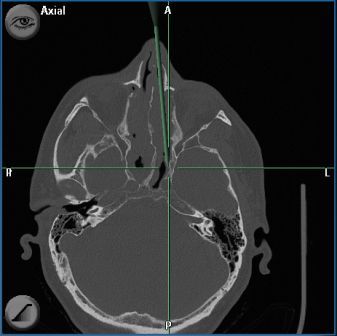

Unterschiedliche Ursachen können zu einer Entzündung der Schleimhaut und Zunahme von entzündlichem Gewebe führen, doch die eigentliche Ursache bleibt dem Patienten oft verborgen. In der Folge werden die Öffnungen der Nasennebenhöhlen verlegt und der Transport von Schleim behindert. Der Schleim sammelt sich in den Nebenhöhlen an. Es kommt dann zu einem Circulus vitiosus entzündlicher Reaktionen. Versagen medikamentöse Behandlungsansätze wie zum Beispiel Antibiotika, kortisonhaltige Nasensprays oder Tabletten, dann wird eine Operation der Nase und der Nasennebenhöhlen notwendig. In der Zusammenschau aller vom Patienten geäußerten Beschwerden, sorgfältiger hno-ärztlicher Untersuchung, röntgenologischen Untersuchungen (Computertomogramm der Nasennebenhöhlen) und Funktionsprüfungen wird für jeden Patienten der beste Weg zur Verbesserung der Situation gesucht.

In der modernen Nasennebenhöhlenchirurgie wird versucht den krankhaften Prozess von der Nase aus zu sanieren und dabei die Funktion von Nase und Nasennebenhöhlen möglichst wenig zu beeinträchtigen. Hierzu werden optische Hilfsmittel wie Mikroskop und Endoskop sowie Spezialinstrumente, ggf. auch der Laser eingesetzt. Bei den entzündlichen Nebenhöhlenerkrankungen liegt das Hauptaugenmerk darauf, möglichst wenig eingreifend (minimal invasiv) vorzugehen, die Engstellen gezielt zu erweitern und gesunde Schleimhaut weitgehend zu erhalten. Der verbleibenden Schleimhaut wird so die Möglichkeit zur Erholung gegeben. An der Hals-Nasen-Ohren-Klinik der Universität Erlangen-Nürnberg wurde schon in den 70-iger Jahren von Prof. Wigand ein weltweit anerkanntes und verwendetes endoskopisch endonasales Konzept der Nasennebenhöhlenchirurgie entwickelt und intensiv sowohl klinisch als auch wissenschaftlich weiterentwickelt. Langzeituntersuchungen bestätigen den Erfolg dieser Methode sowohl durch langfristige Beschwerdelinderung bei ca. 80% aller operierten Patienten, als auch durch Besserung von asthmoiden Beschwerden, chronischen Bronchitiden und Infektanfälligkeit. Aber nicht nur bei der Behandlung von chronisch entzündlichen Erkrankungen der Nasennebenhöhlen sondern auch bei der Behandlung akuter Komplikationen und Tumorerkrankungen hat sich das minimal invasive Konzept der endonasalen endoskopischen Nasennebenhöhlenchirurgie bewährt. Mit der Computersassistierten-Chirurgie (CAS) stehen Verfahren zur Verfügung die eine sicheres und exaktes Entfernen von erkranktem Gewebe ermöglichen. Anhand einer individuellen Beratung wird das Ausmaß der Operation festgelegt.